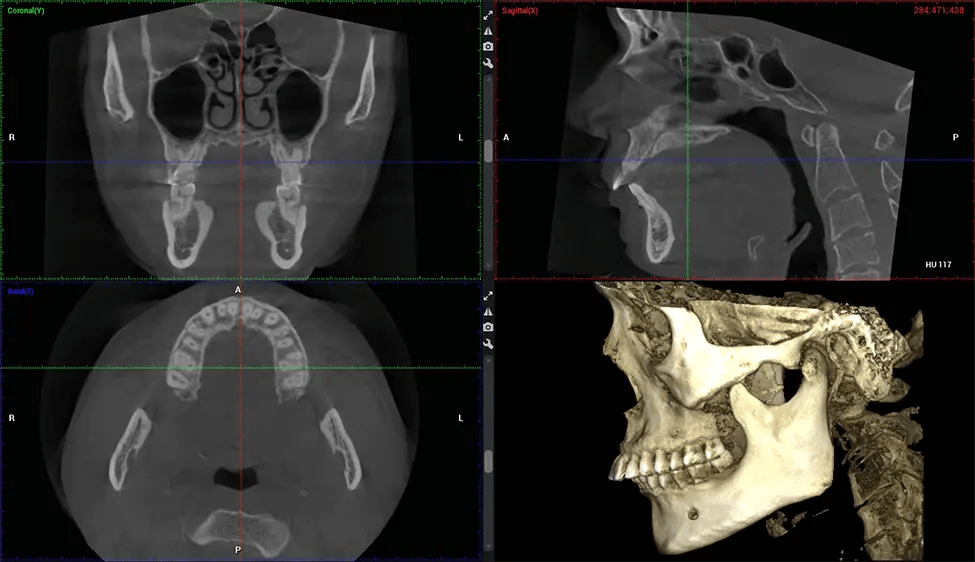

Cone Beam Computed Tomography (CBCT) is an advanced imaging technique used in dentistry and maxillofacial surgery to obtain detailed 3D images of the oral and maxillofacial structures. At Dr G Dental Studio, our CBCT scanners utilize a cone-shaped X-ray beam and a specialized detector to capture images from different angles. A computer then combines these images to create a 3D representation of the patient’s oral anatomy.

This 3D scan, called cone beam computed tomography, gives your dentist a more complete image of your oral anatomy and disease processes than a traditional X-ray. Unlike conventional X-rays, which capture a 2D image of your mouth from various angles, a 3D scan takes multiple digital X-rays for one image. It provides a complete view of your jaw, teeth, nerves, and soft tissues. This enhanced view allows dentists to detect minor issues not visible in traditional 2D scans, such as impacted wisdom teeth or bone fractures in the sinus cavity.

The patient is first positioned in the CBCT scanner, which typically consists of a rotating arm that houses the X-ray source and a detector. The patient’s head is immobilized to ensure accurate image capture. The X-ray source and detector rotate around the patient’s head, capturing various X-ray images from multiple angles. As the X-ray source rotates, it emits the cone-shaped X-ray beam towards the detector. The detector captures the X-ray images, which are then processed by the CBCT software.

After the scanning process, the captured X-ray images are processed by the CBCT software, which applies algorithms to reconstruct a detailed 3D image of the scanned area. The software compiles these individual X-ray images and creates a digital 3D representation of the patient’s anatomy. The reconstructed 3D CBCT image can be viewed and analyzed by the dentist or radiologist. This image can be manipulated, rotated, and zoomed in or out to examine specific structures and evaluate the patient’s condition.

Planmeca Viso G7 CBCT ( Cone Beam CT Scan ) is designed to surpass the demands of industry leaders, specialists, and large institutions. It’s has a large ø25×30 cm sensor with four built-in cameras. It can capture unlimited volume sizes from a ø3×3 cm to a ø30x30cm volume capturing the skullcap through C7 on the cervical spine. The Planmeca Viso G7 offers the industry’s largest single volume scan of ø30×19 cm. It’s poised to handle advanced imaging modalities such as Planmeca ProFace® and Planmeca 4D™ Jaw Motion technology. The occipital head support allows an unimpeded view of facial tissue.